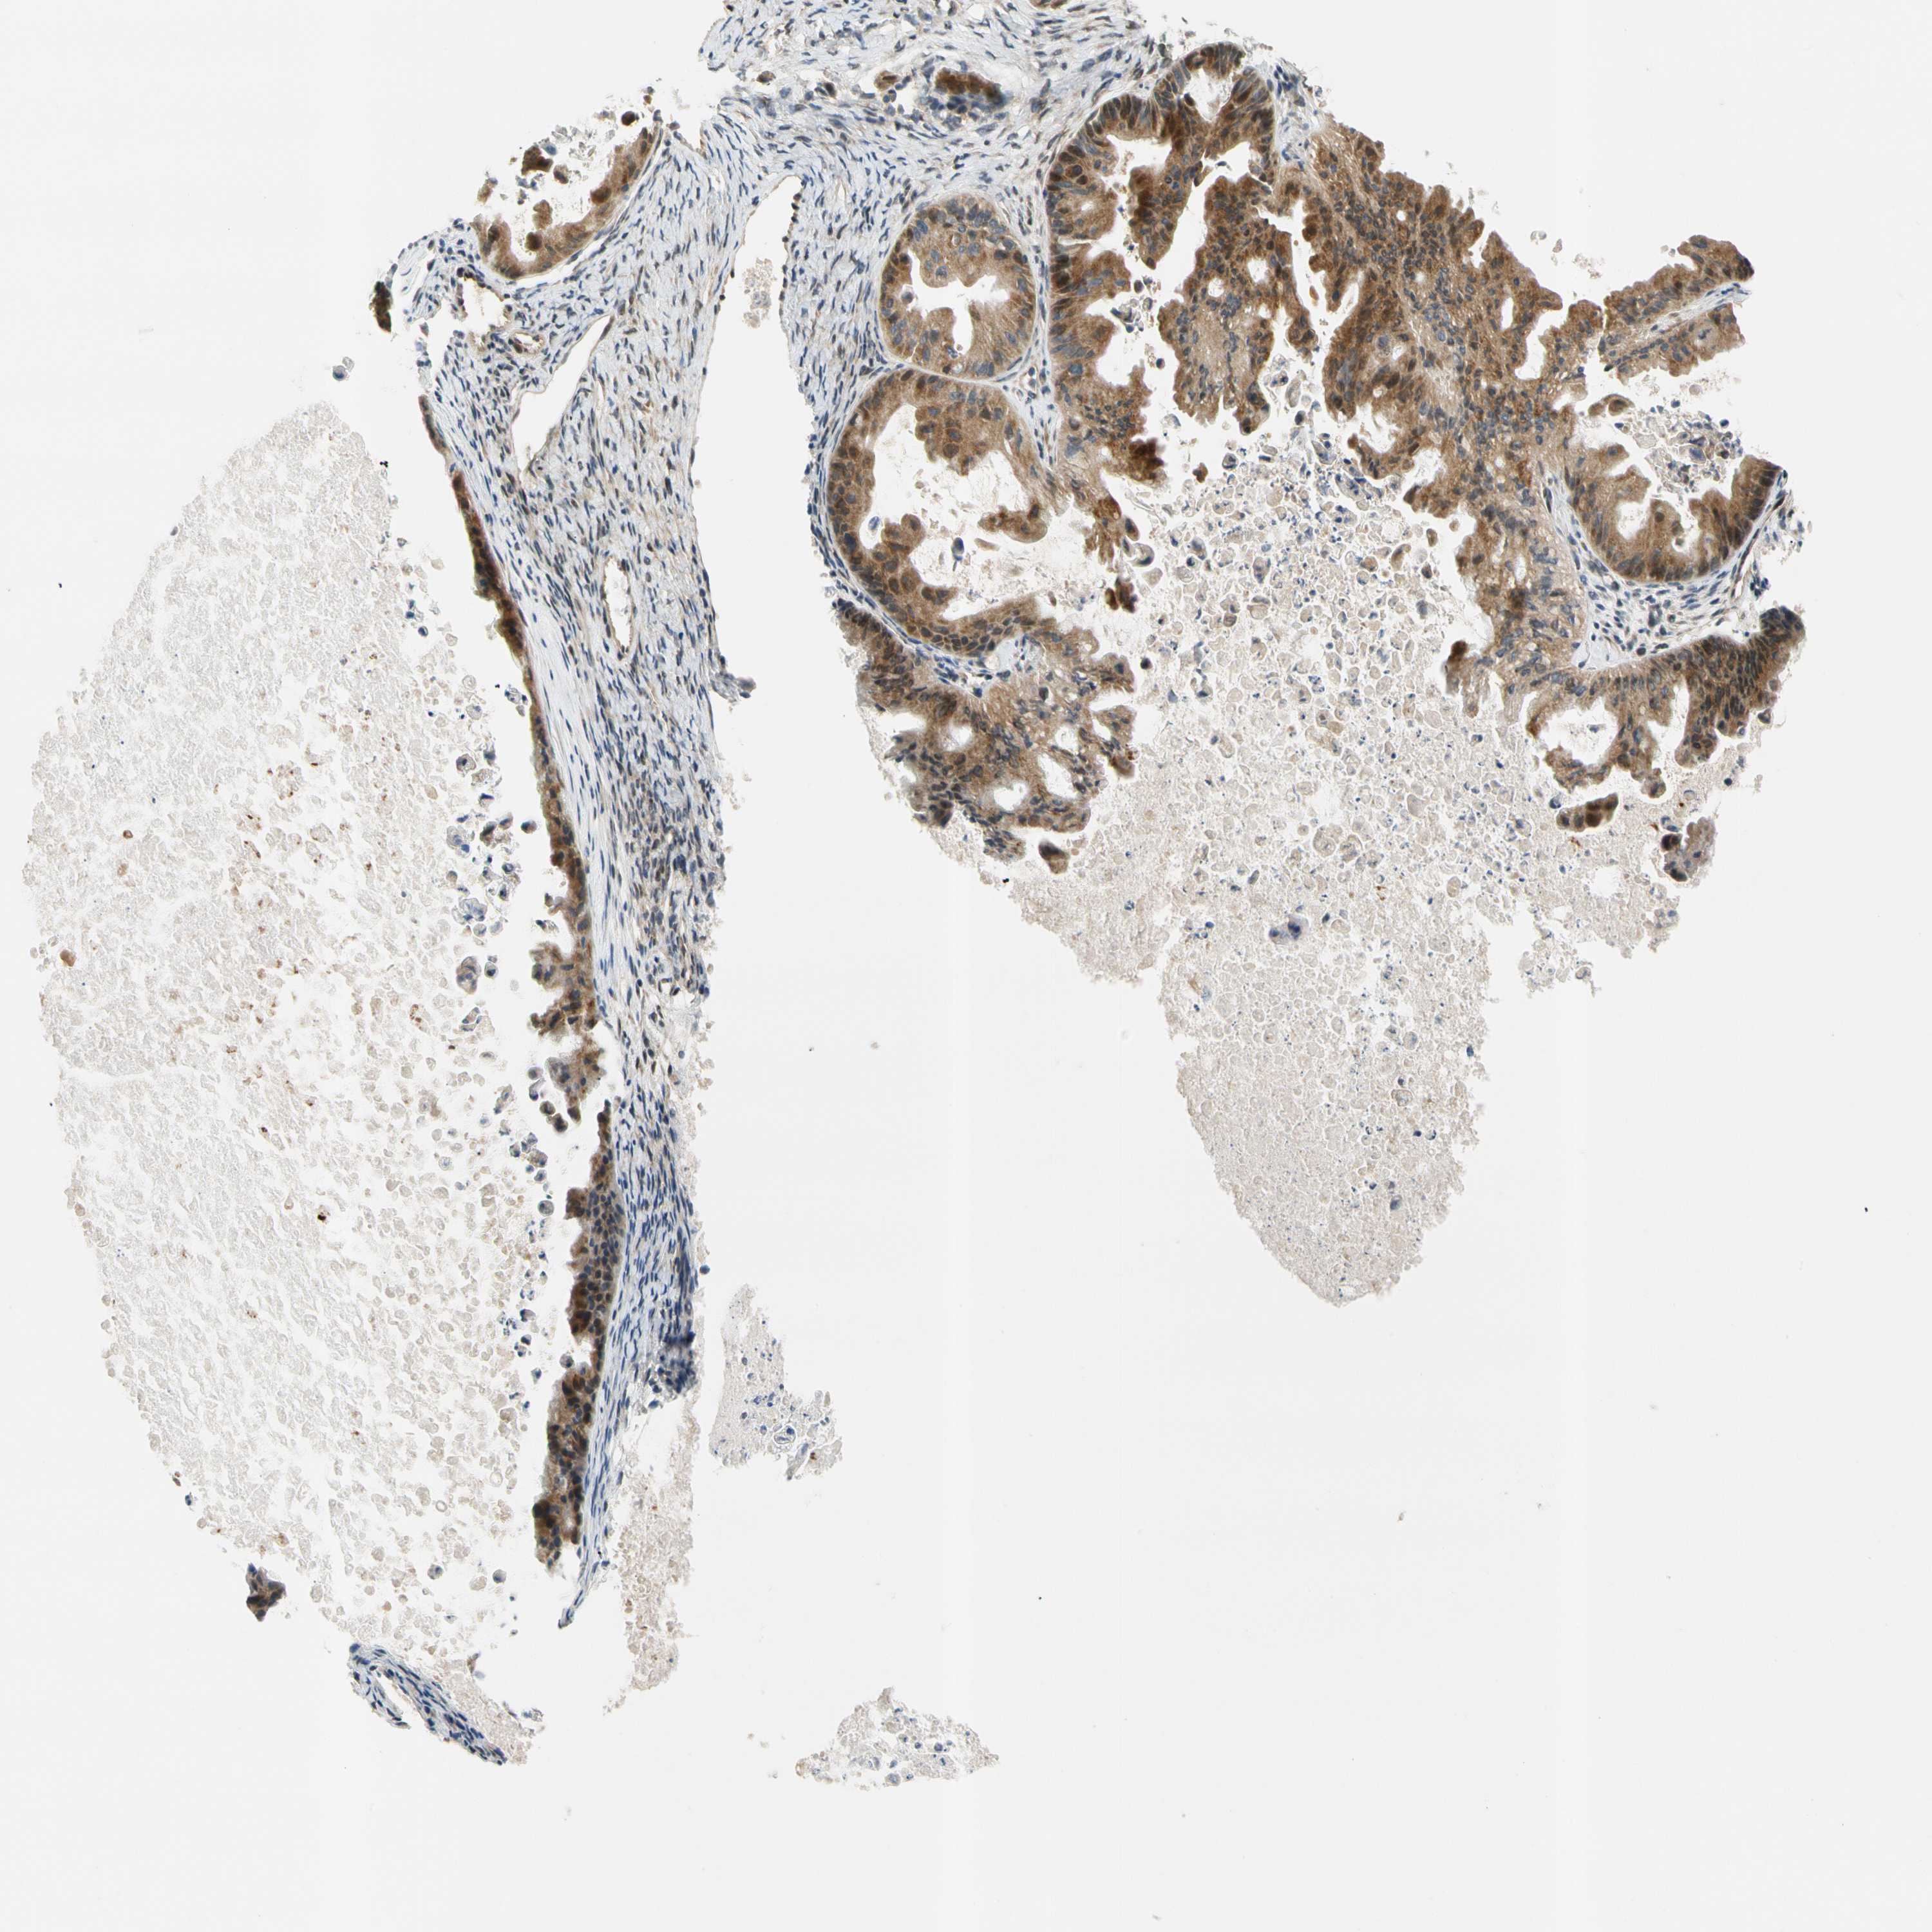

OVARIAN CANCER - Protein expressioni

A mouse-over function shows sample information and annotation data. Click on an image to view it in a full screen mode. Samples can be filtered based on level of antibody staining by selecting one or several of the following categories: high, medium, low and not detected. The assay and annotation is described here.

Note that samples used for immunohistochemistry by the Human Protein Atlas do not correspond to samples in the TCGA dataset.

Antibody stainingi

Antibody staining in the annotated cell types in the current human tissue is reported as not detected, low, medium, or high, based on conventional immunohistochemistry profiling in selected tissues. This score is based on the combination of the staining intensity and fraction of stained cells.

Each image is clickable and will lead to virtual microscopy that enables deeper exploration of all samples and also displays staining intensity scores, fraction scores and subcellular localization as well as patient and tissue information for each sample.

Antibody HPA008812

Staining

High

Medium

Low

Not detected

Intensity

Strong

Moderate

Weak

Negative

Quantity

>75%

75%-25%

<25%

None

Location

Nuclear

Cytoplasmic/membranous

Cytoplasmic/membranous,nuclear

Cystadenocarcinoma, serous, NOS

Carcinoma, endometroid

Cystadenocarcinoma, mucinous, NOS

Carcinoma, NOS